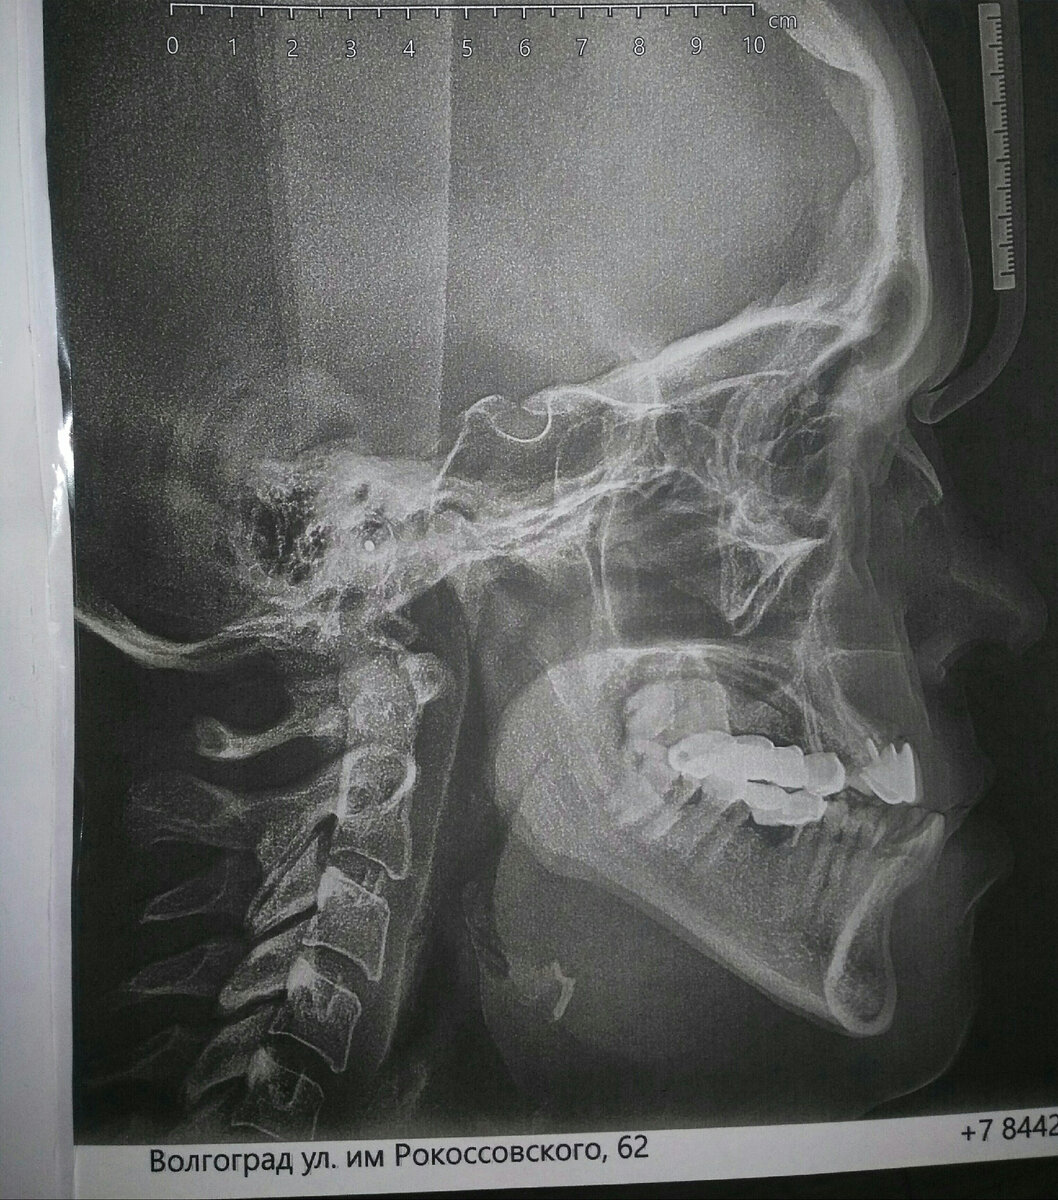

ТРГ автора.